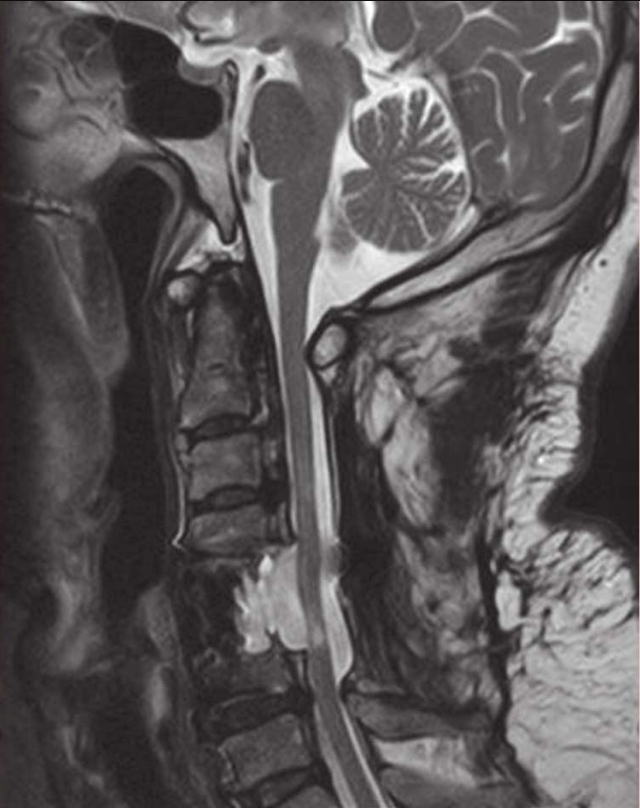

术后给予激素、补液及支持对症治疗,右手麻木较前好转,右侧肢体出现无力,左侧肢体出现麻木,疼痛感不明显,经康复治疗后,右手环指及小指仍感无力,余肢体麻木及无力较前好转,仍对生活及工作有影响。复查颈椎磁共振(MRI)示:C2-6椎板减压及内固定术后状态(图2),C4-6脊髓稍变细,以 C5-6节段显著,C2-6后纵韧带钙化(图2);CT三维重建钉棒系统位置良好(图3);术后3个月复查磁共振(MRI),髓内异常信号较前缩小,颈椎生理曲度变直(图4);术后11个月复查磁共振(MRI)示C4-5、C4-6椎间盘突出,脊髓受压明显,颈椎生理曲度进一步变直(图5)。

图5 术后11个月磁共振(MRI)示C4-5、C4-6椎间盘突出,脊髓受压明显

a. 矢状位T1像;b.矢状位T2像